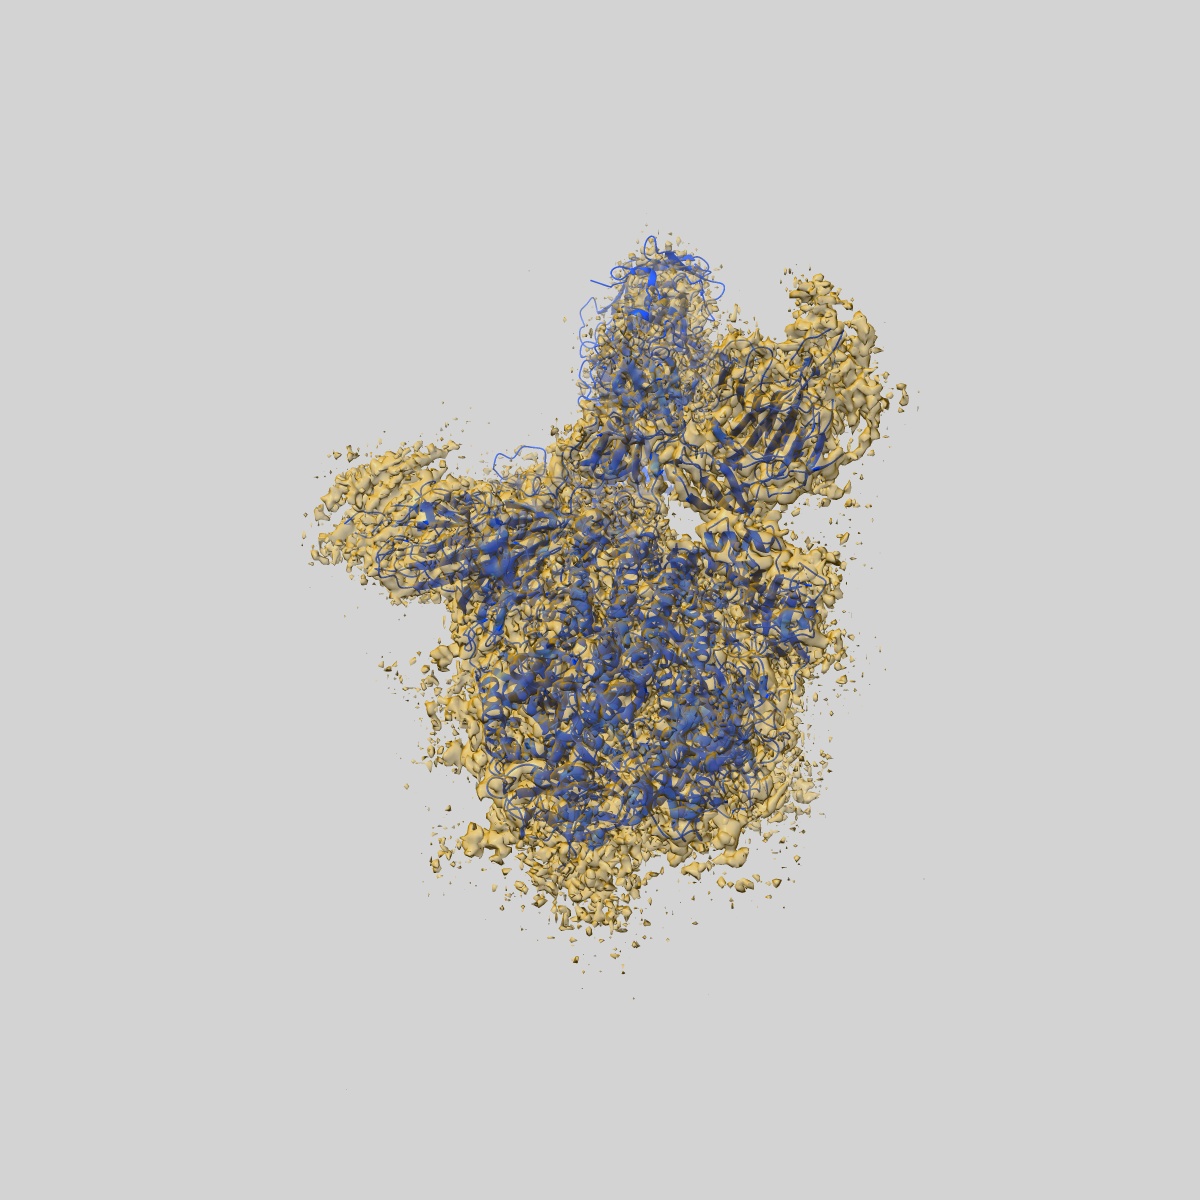

EMD-30516

S protein of SARS-CoV-2 in complex bound with P5A-2G9

Single-particle2.7 Å

Sample: S protein of SARS-CoV-2 in complex bound with P2B-2G9

Fitted models: 7czt